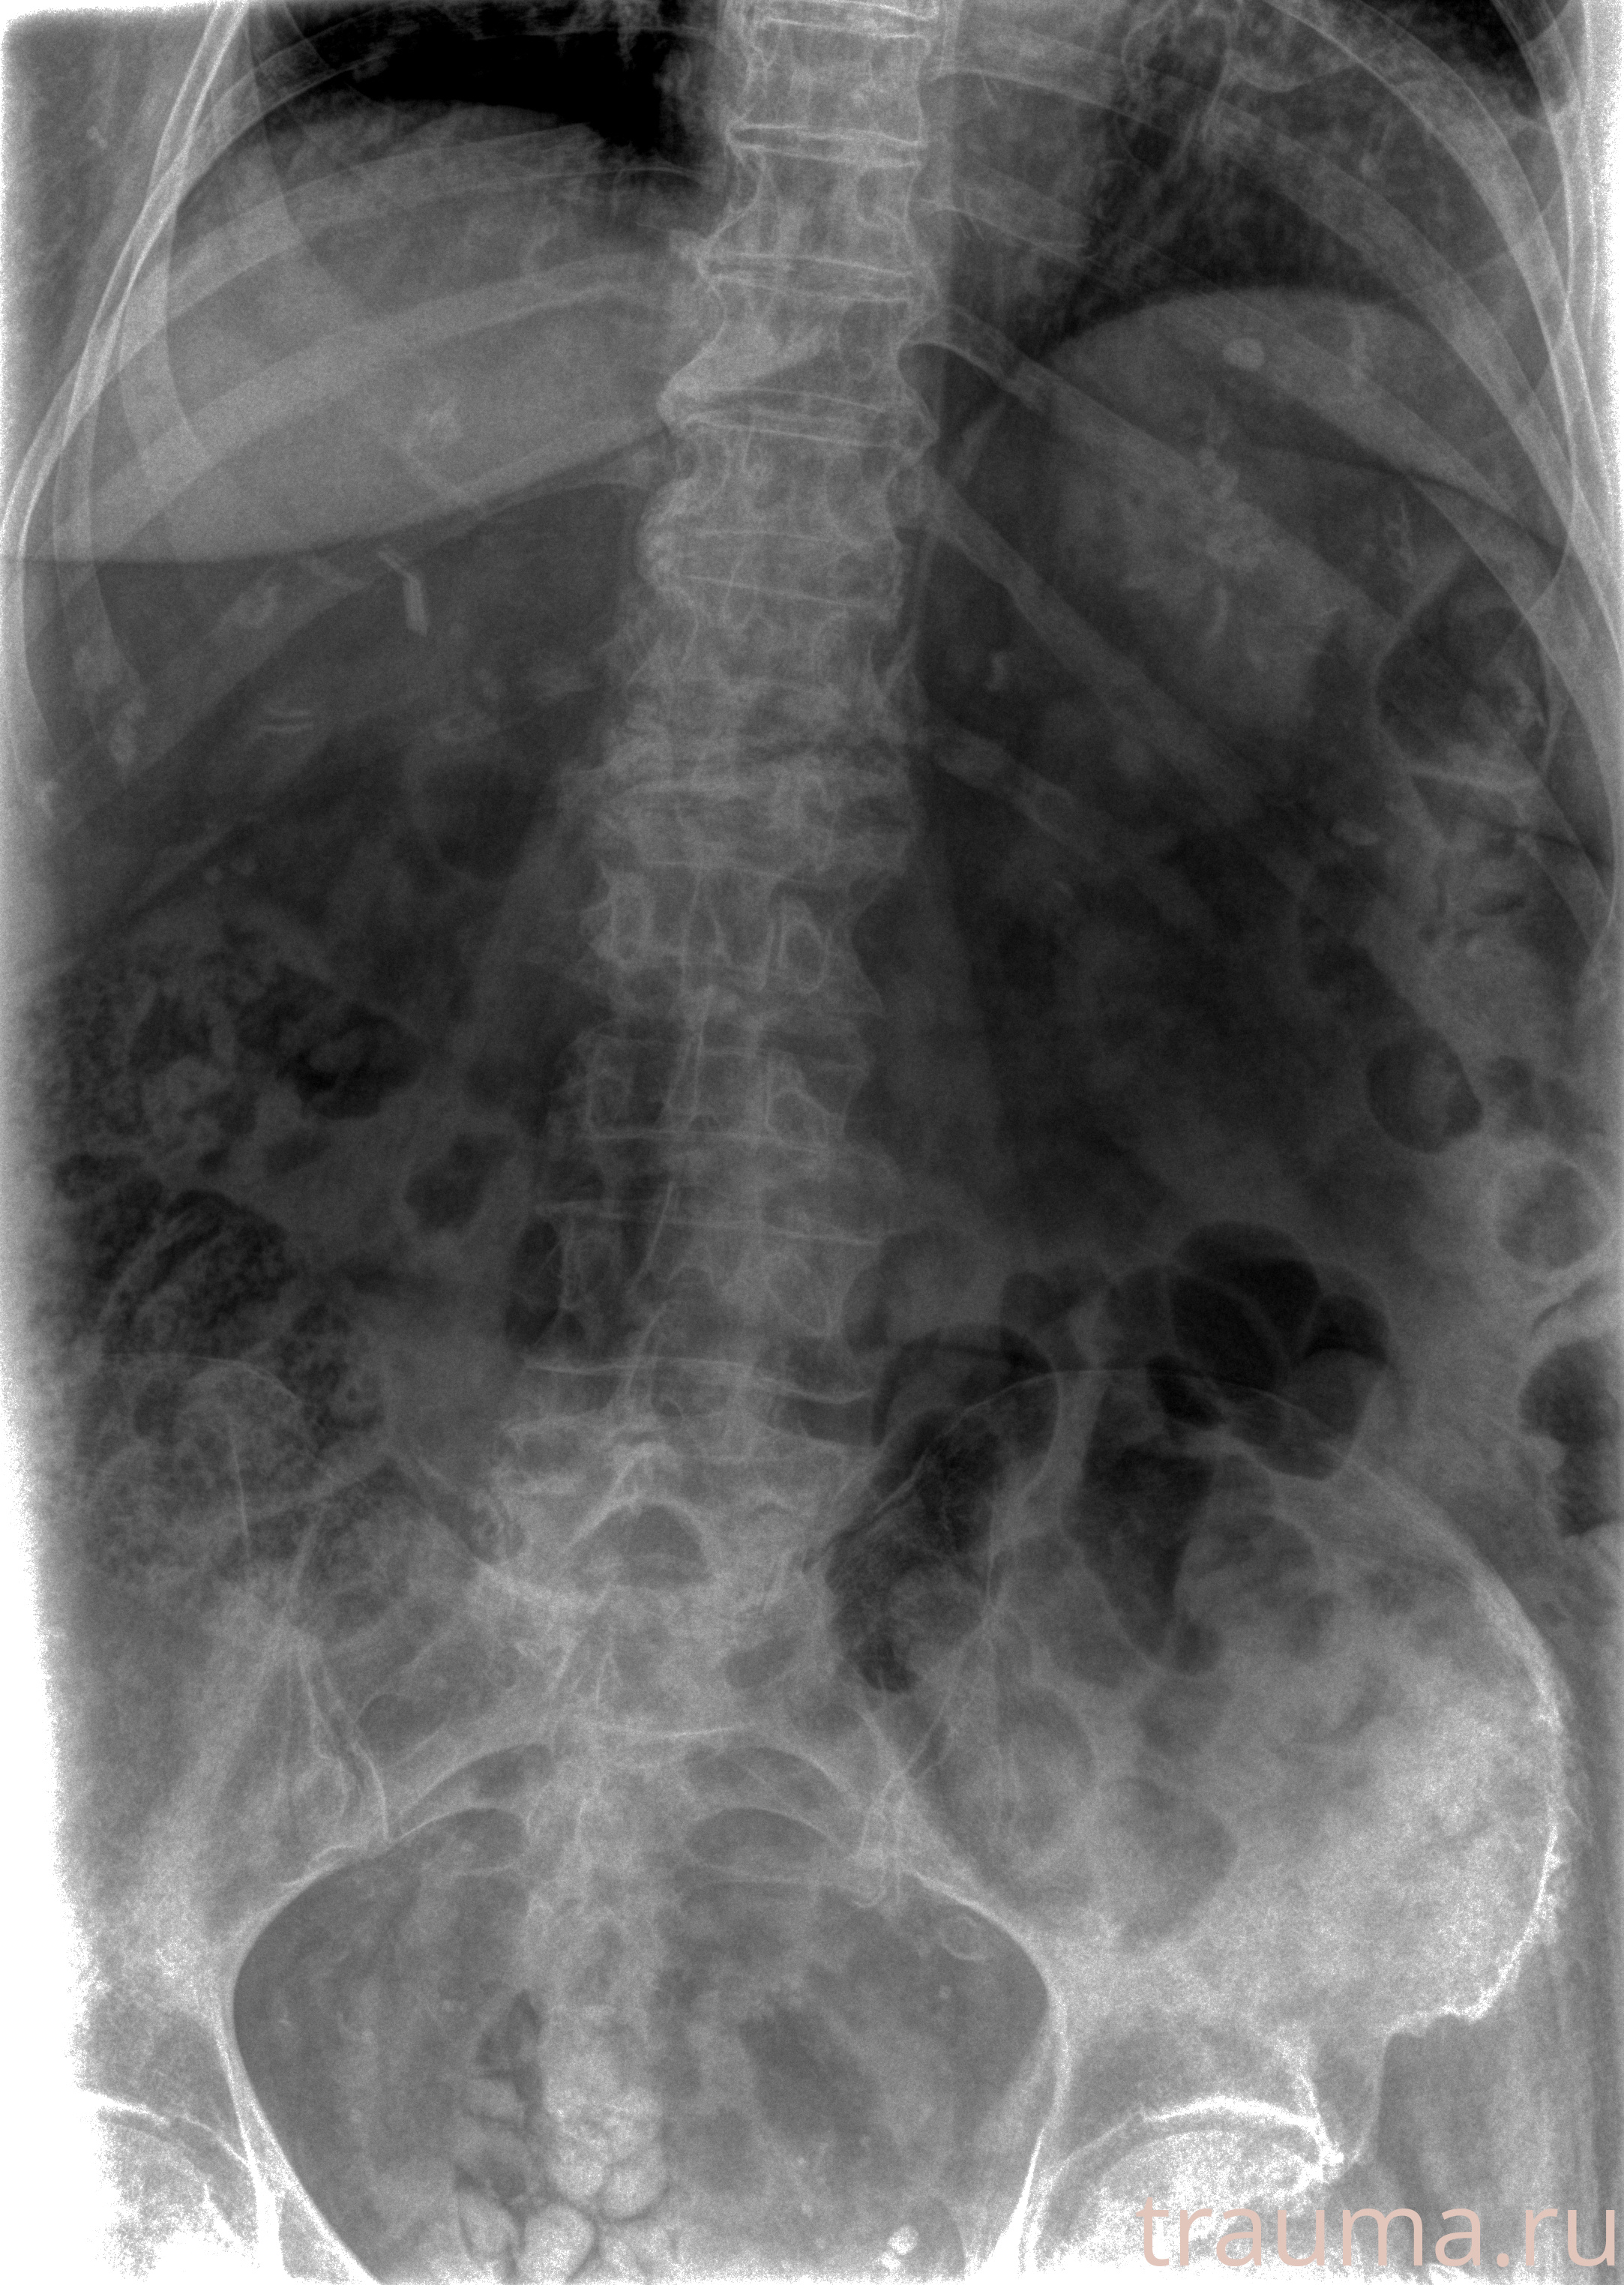

Рентгенограммы

Рентген на дому: по вашему адресу приезжает врач-рентгенолог, травматолог-ортопед с мобильным рентгеновским аппаратом, проводит диагностику травмы или заболевания, делает необходимые рентгенограммы, дает рекомендации по дальнейшему лечению. Получить качественные снимки в домашних условиях возможно благодаря уникальной методике, разработанной МосРентген Центром для института  Склифосовского